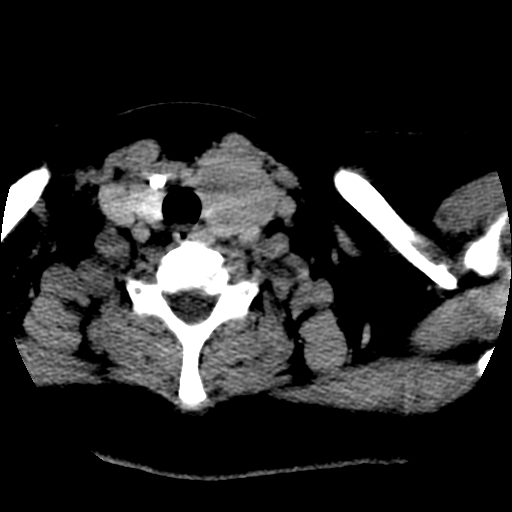

标题: CT25491:女,55岁,发现左侧甲状腺肿块一个月。 [打印本页]

标题: CT25491:女,55岁,发现左侧甲状腺肿块一个月。

女,55岁,发现左侧甲状腺肿块一个月,彩超示:甲状腺多发结节伴左叶结节液化。

腺瘤囊变

考虑左侧甲状腺腺瘤囊变。